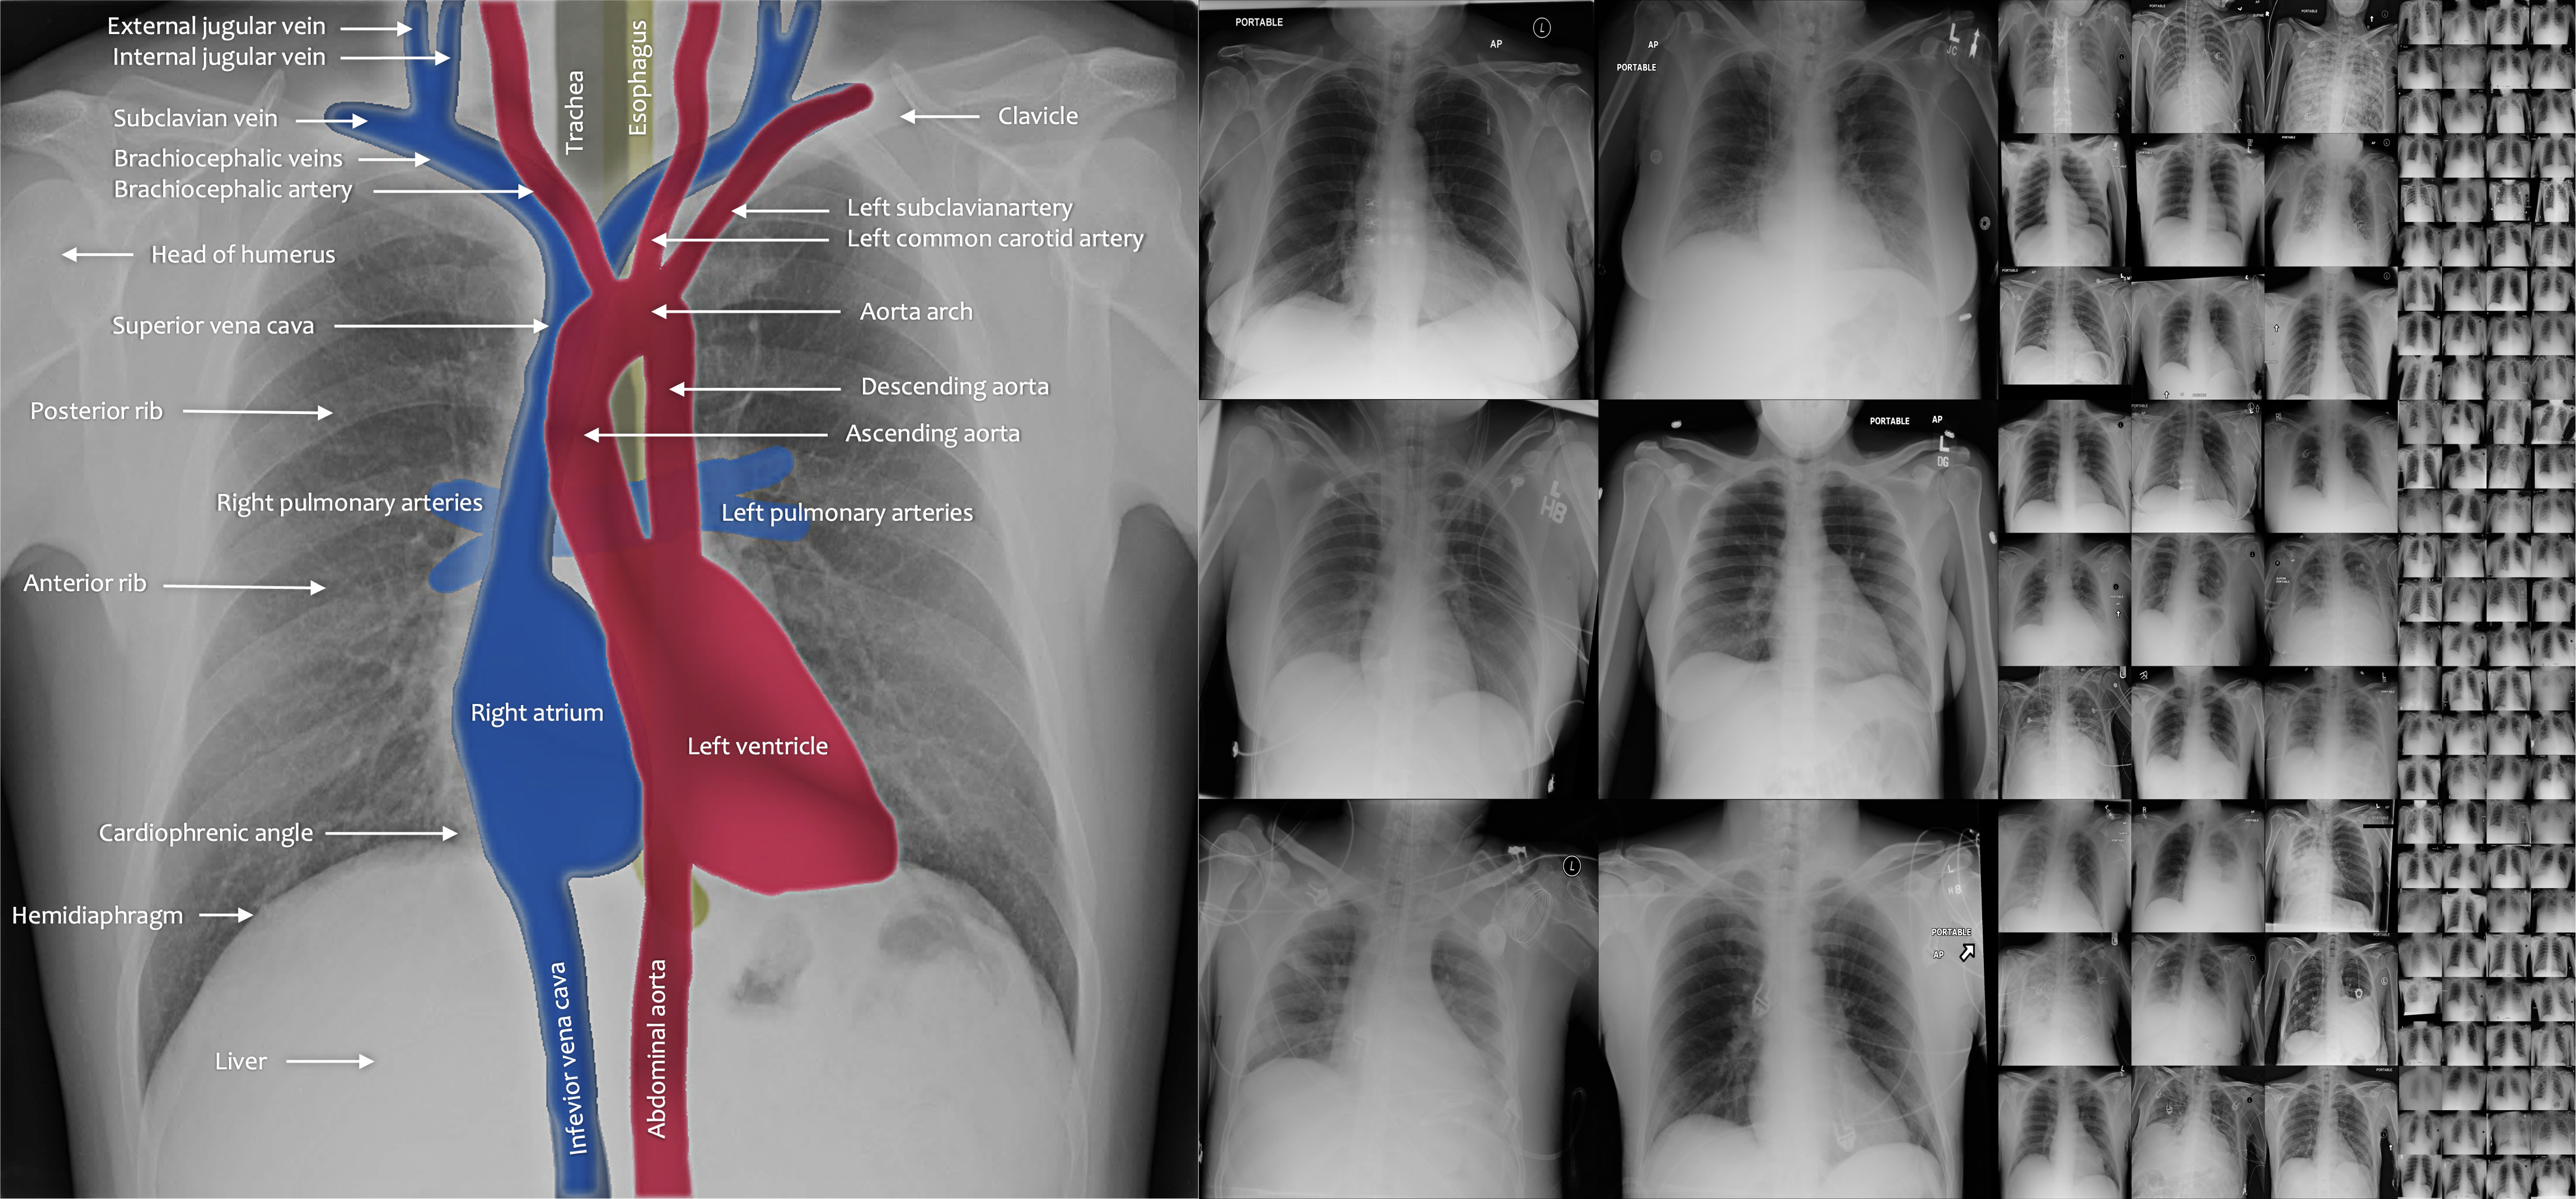

Vision tasks in photographic and radiographic images differ significantly. In photographic object identification, the object’s location within the image is typically less important—a cat remains a cat regardless of its position within the image. Conversely, in radiography, the relative location and orientation of anatomical structures are crucial for both identifying normal anatomy and recognizing pathologies [1, 2, 3, 4, 5]. Due to standardized imaging protocols in radiography, images exhibit a high degree of similarity across patients, equipment manufacturers, and institutions (see examples in Figure 1). Consistent and recurrent anatomy can facilitate the analysis of numerous critical problems and should be considered a significant advantage of radiography imaging. For example, several investigations have demonstrated the value of harnessing this prior knowledge to enhance Deep Nets’ performance, such as adding location features, modifying objective functions, and constraining coordinates relative to landmarks in images [6, 7, 8, 9, 10, 11, 12]. This paper focuses on unsupervised anomaly detection, seeking to answer the critical question: Can we exploit consistent anatomical patterns and their spatial information to strengthen Deep Nets in detecting anomalies from radiography images without manual annotation?

Refer to caption

Figure 1: Anomaly detection in radiography images can be both easier and harder than photographic images. It is easier because radiography images are spatially structured due to consistent imaging protocols. It is harder because anomalies are subtle and require medical expertise to annotate. We contribute a novel anomaly detection method (SimSID) that directly exploits the structured information in radiography images.

Differing from photographic images, radiography imaging protocols produce images with consistent anatomical patterns, and meanwhile, the anomalies in radiography images can be subtle in appearance and hard to interpret (Figure 1). Unlike most existing works, we present a novel method that explicitly harnesses the radiography images’ properties, therefore dramatically improving the performance in anomaly detection from radiography images.